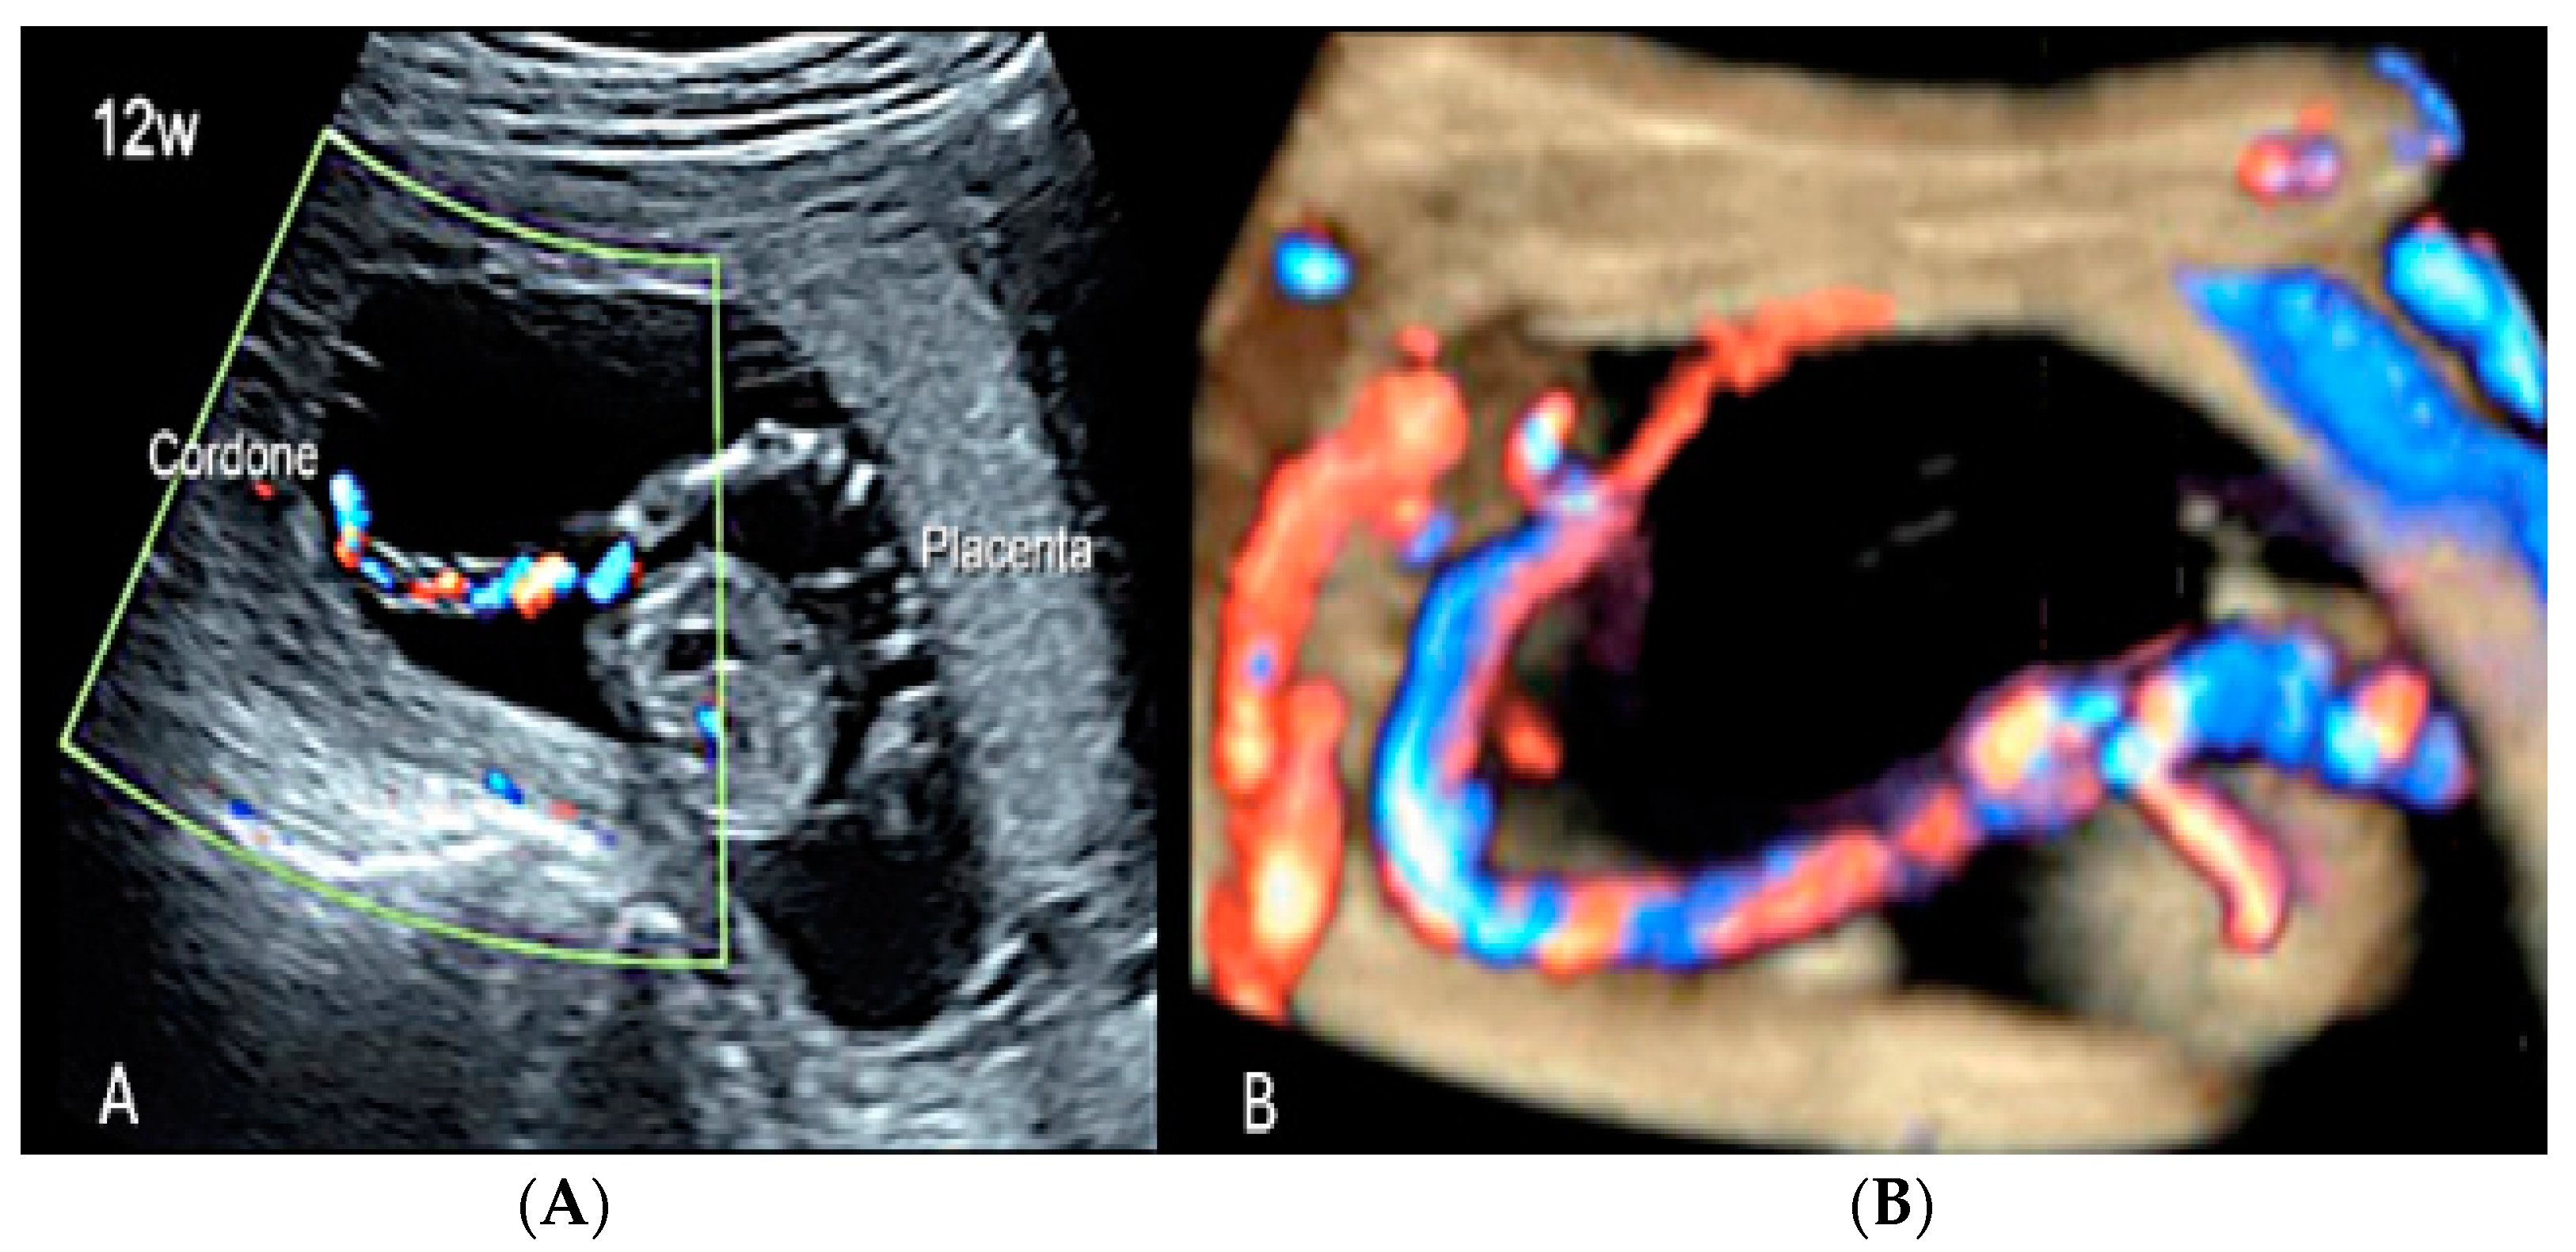

Figure 18.

(A,B) First trimester (12 weeks) scan showing in two-dimensional- and three-dimensional color Doppler ultrasound a velamentous cord insertion (Cordone: umbilical cord).

Figure 19.

Pregnancy at 19 week’s gestation (same case of the previous figure). Two-dimensional color Doppler ultrasound (A) and four-dimensional color Doppler STIC volume (B) diagnosed velamentous cord insertion.